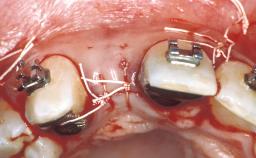

In September of 1995, a 64-year-old female patient presented to our clinic with a distally shortened arch in the left maxilla and the desire for a fixed rehabilitation. The patient’s medical history did not reveal any major issues, and she did not take any significant medication. She was a non-smoker and did not report any allergies.The patient wished to restore her chewing function on the left side, which was severely compromised due to the missing teeth 25, 26, and 27. The antagonistic lower teeth were present and in acceptable condition.

Bone Augmentation | No|Sinus Floor Elevation|Staged |

Bone Volume | Deficient vertically or deficient vertically AND horizontally |

Anatomic Risk | High |

Complexity | High |

Risk of Complications | High |